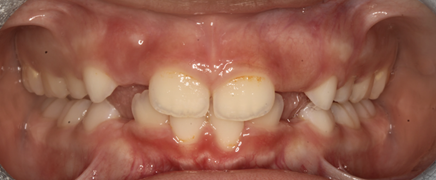

Después de 6 meses de tratamiento y activaciones de los aparatos, se consiguió corregir la mordida cruzada anterior.

Figura 14. Corrección de mordida cruzada anterior

Se observa que los incisivos laterales superiores permanentes no tienen espacio para erupcionar, por lo cual se recomienda la extracción de los caninos superiores deciduos.